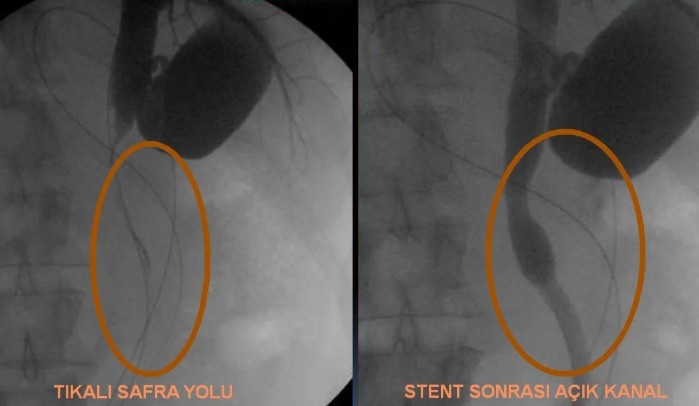

• ERCP ile safra yolu taşının çıkarılması veya stent yerleştirilmesi